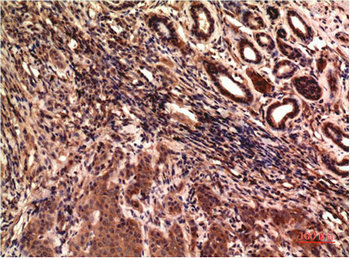

Immunohistochemical analysis of paraffin-embedded Human Breast Carcinoma Tissue using TUBG1 Monoclonal Antibody diluted at 1:200.